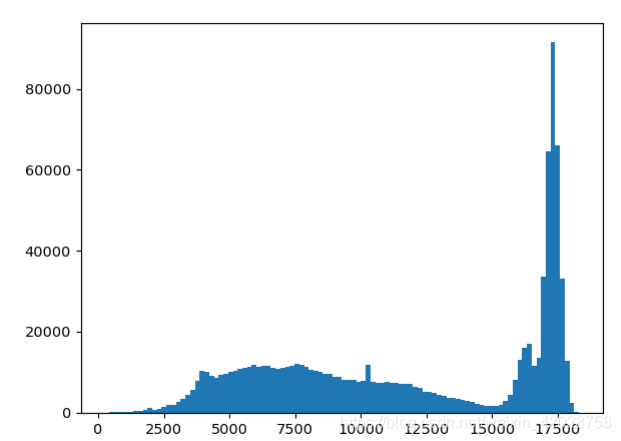

显示一张图的灰度直方图分布

intensity_profile_image =ankle_image

fig = plt.figure()

plt.hist(sitk.GetArrayViewFromImage(intensity_profile_image).flatten(),bins=100);

我们可以观察到,图像有一个高动态的范围。在显示时映射到一个低动态范围,因此我们不能观察所有潜在的强度变化。理想情况下,x射线图像的强度变化只发生在被成像对象发生变化时。